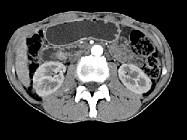

问题 男,48岁,进行性黄疸,发热,腹胀,影像检查如图,最佳的诊断是()

选项 A.胆总管囊肿 B.胆总管结石 C.胆总管癌 D.十二指肠乳头癌 E.胰头癌

答案 D